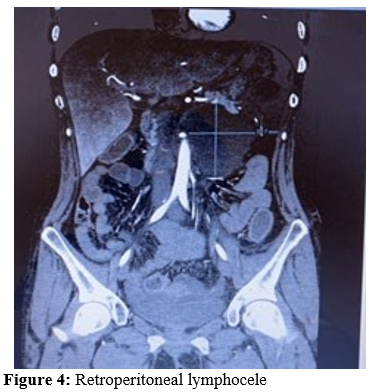

The superior mesenteric artery (blue arrow) after transposition with a normal aortomesenteric angle. Previous orifice of the su¬perior mesenteric artery (red arrow) and celiac trunk (yellow arrow). CTA: computed tomography angiography One patient (2.7%), four-day postoperatively, had a lymphocele formed in the retroperitoneum, which was successfully drained by a CT-guided percutaneous pigtail cath

One patient (2.7%) needed a relaparotomy 3-month postopera¬tively due to adhesions that had formed around the duodenum leading to duodenal compression in the second segment for which we performed adhesiolysis and omentoplasty. One patient (2.7%), 2-year postoperatively, had a proximal SMA stenosis up to 60% where drug-eluting balloon percutaneous translumi¬nal angioplasty (DEB PTA) was performed successfully (Fig-ures6-7).